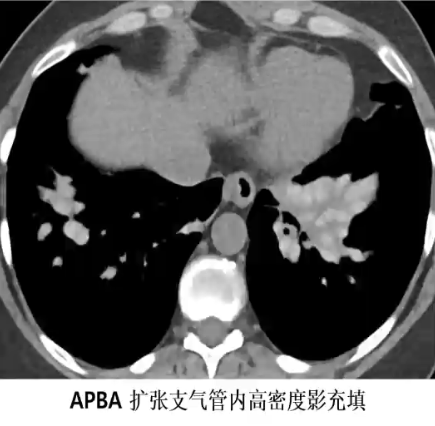

支气管肺曲霉菌病(ABPA)

❖ 长期支气管哮喘者常见上叶常见,囊状或静脉曲张状支气管扩张,其内可见粘液嵌塞,表现为肺门旁增粗的分支状影(指套征),增强扫描无明显强化

❖ 扩张支气管内高密度或钙化粘液栓(19-28%)具有较高特异性,提示ABPA较为严重,易复发